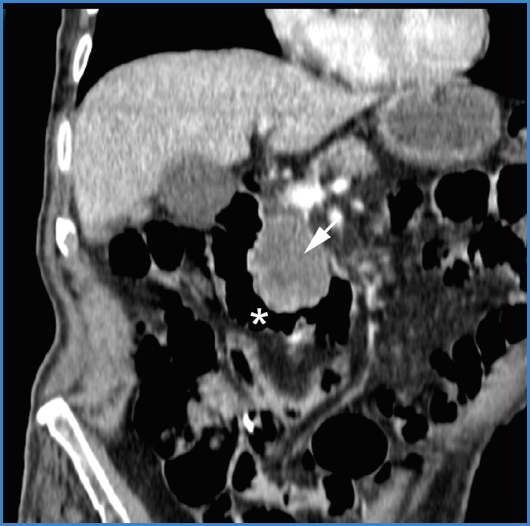

Las manifestaciones clínicas suelen ser fiebre y dolor abdominal, que en general se acompañan de leucocitosis y hemocultivos positivos, mientras que la presencia de inflamación de los tejidos blandos periaórticos en la tomografía refuerzan el diagnóstico de aneurisma micótico.[4]

El diagnóstico debe basarse en la sospecha clínica apoyada en las técnicas de imagen, como la angiografía y la tomografía computarizada (TC), técnica de elección para la detección del aneurisma. La TC es decisiva en el diagnóstico de los aneurismas micóticos. Una vez detectados deben tratarse sin demora, pues su evolución natural es hacia la rápida expansión y rotura. La angiografía ayuda a planificar el tratamiento. La radiología intervencionista representa un papel importante en el tratamiento.[4]